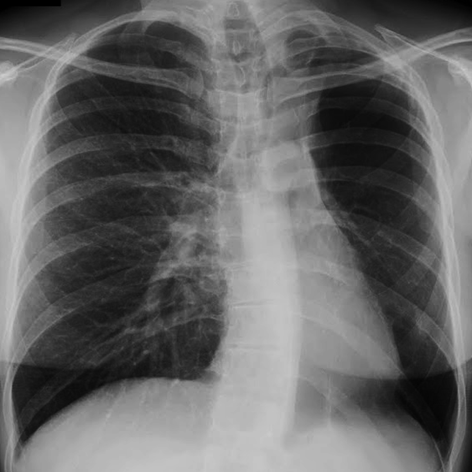

Chest X-ray (PA view):

Chest Radiograph

• Unilateral hyperlucency of the affected lung or lobe.

• Decreased vascular markings (oligemia).

• Small hemithorax with mediastinal shift toward the affected side.

• Compensatory hyperinflation of the contralateral lung.

• Unilateral hyperlucencyThe affected lung appears more radiolucent (darker) due to decreased pulmonary vascular markings and air trapping.

• Reduced pulmonary vasculatureThere is a noticeable decrease in the size and number of pulmonary vessels on the affected side.

• Small or normal lung volumeThe affected lung may be slightly reduced in volume or appear normal, depending on the extent of involvement.

• Elevated hemidiaphragmThe diaphragm on the affected side may be elevated due to volume loss.

• Mediastinal shiftIn some cases, there may be a shift of mediastinal structures toward the affected side.

Typical imaging features of Swyer-James-MacLeod syndrome secondary to post-infectious obliterative bronchiolitis, with unilateral hypoperfused lung, bronchiectasis, and air trapping.